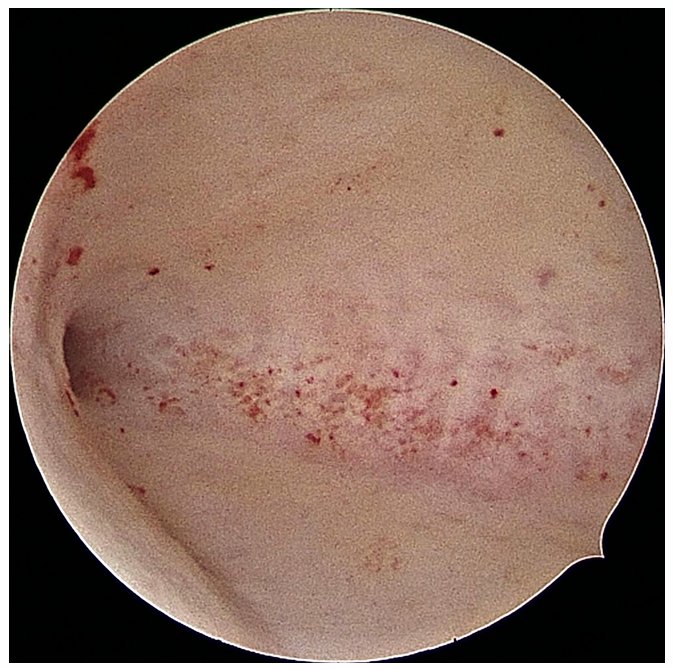

Thanks to advancements in technology, we now use smaller diameter hysteroscopes (some as thin as 3 to 5mm). This offers significant benefits to our patients:

● Minimally Invasive: It avoids the risks of major surgery.

● Accuracy: Unlike “blind” procedures like D&C (Dilation and Curettage), hysteroscopy allows us to see exactly where the problem is, ensuring we don’t miss focal pathology.

● Quick Recovery: Most patients go home the same day and resume normal activities within 24 hours.

● See and Treat: We can often diagnose and fix the problem in a single visit, streamlining your treatment plan.